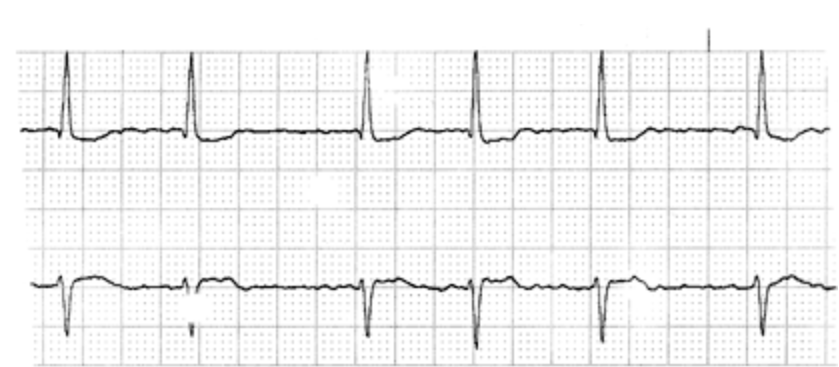

A 52-year-old man is brought to the emergency department because of a 6-hour history of thirst and fatigue and a 2-hour history of light-headedness. He has been working outside during the past 2 days in temperatures reaching 90.0°F. He has no history of serious illness and takes no medications. On arrival, he is lethargic. He is oriented to person but not to place or time. His temperature is 37.2°C (99.0°F), pulse is 74/min and irregular, respirations are 16/min, and blood pressure is 95/64 mm Hg. The lungs are clear to auscultation. No bruits are heard. No murmurs are heard on cardiac examination. The abdomen is nontender. ECG is shown. In addition to intravenous administration of fluids, which of the following is the most appropriate next step in management?